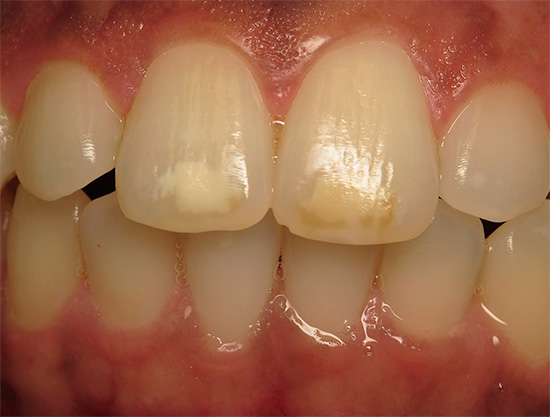

Ad esempio, ecco i denti anteriori con macchie bianche nella foto - i fuochi della carie iniziale: